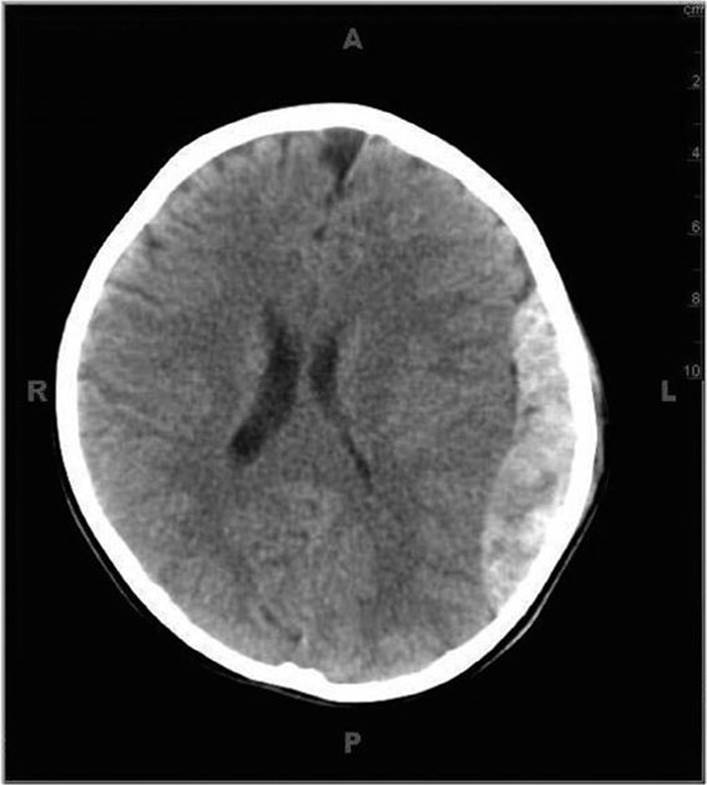

Epidural hematomas occur more commonly in older children than in infants and toddlers.6 Most occur in combination with a temporal skull fracture and meningeal artery bleeding; the remainder are venous in origin. They may be life-threatening, but prompt diagnosis and surgical intervention make an excellent outcome possible. Signs and symptoms include headache, vomiting, and altered mental status, which may progress to signs and symptoms of uncal herniation with pupillary changes and hemiparesis. Patients classically present with an initial lucid period followed by a rapid deterioration in mental status as the hemorrhage increases in size (Fig. 23-2).

FIGURE 23-2. Epidural hematoma with midline shift.